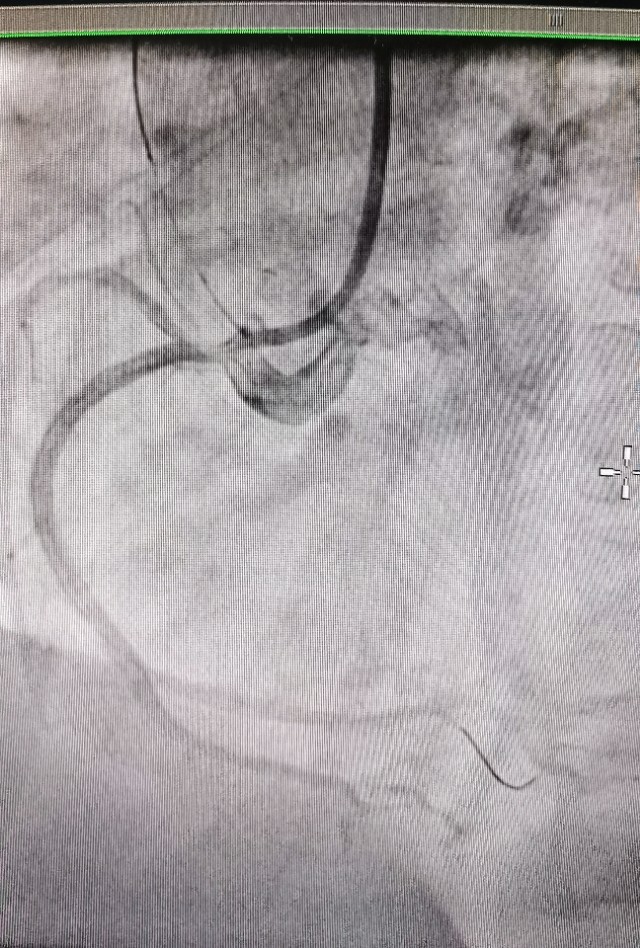

病例1 发现开口病变,精准植入支架

中年女性,劳力性胸闷多年,造影发现Guilding“嵌顿”现象,OCT发现开口严重狭窄,药物球囊治疗后效果良好。